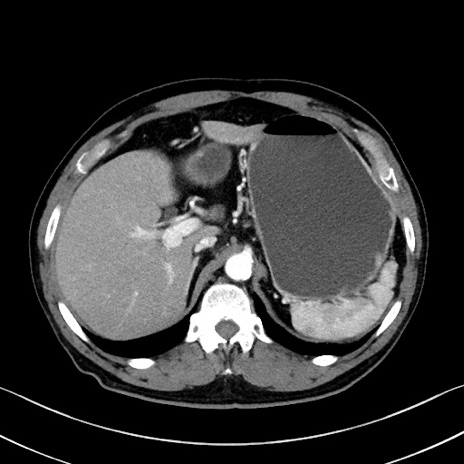

冠状断像

【症例】70歳代 男性

【主訴】腹部膨満、嘔吐

【現病歴】昨日より腹部膨満感出現。本日増悪し、仙痛出現。嘔吐あり、受診。

【既往歴】糖尿病、胆摘後

【身体所見】BP 149/80mmHg、HR 74/min、BT 35.9℃、腹部:膨満、軟、圧痛なし。腸雑音減弱あり。上腹部正中切開瘢痕あり。

【データ】WBC 13500、CRP 1.72